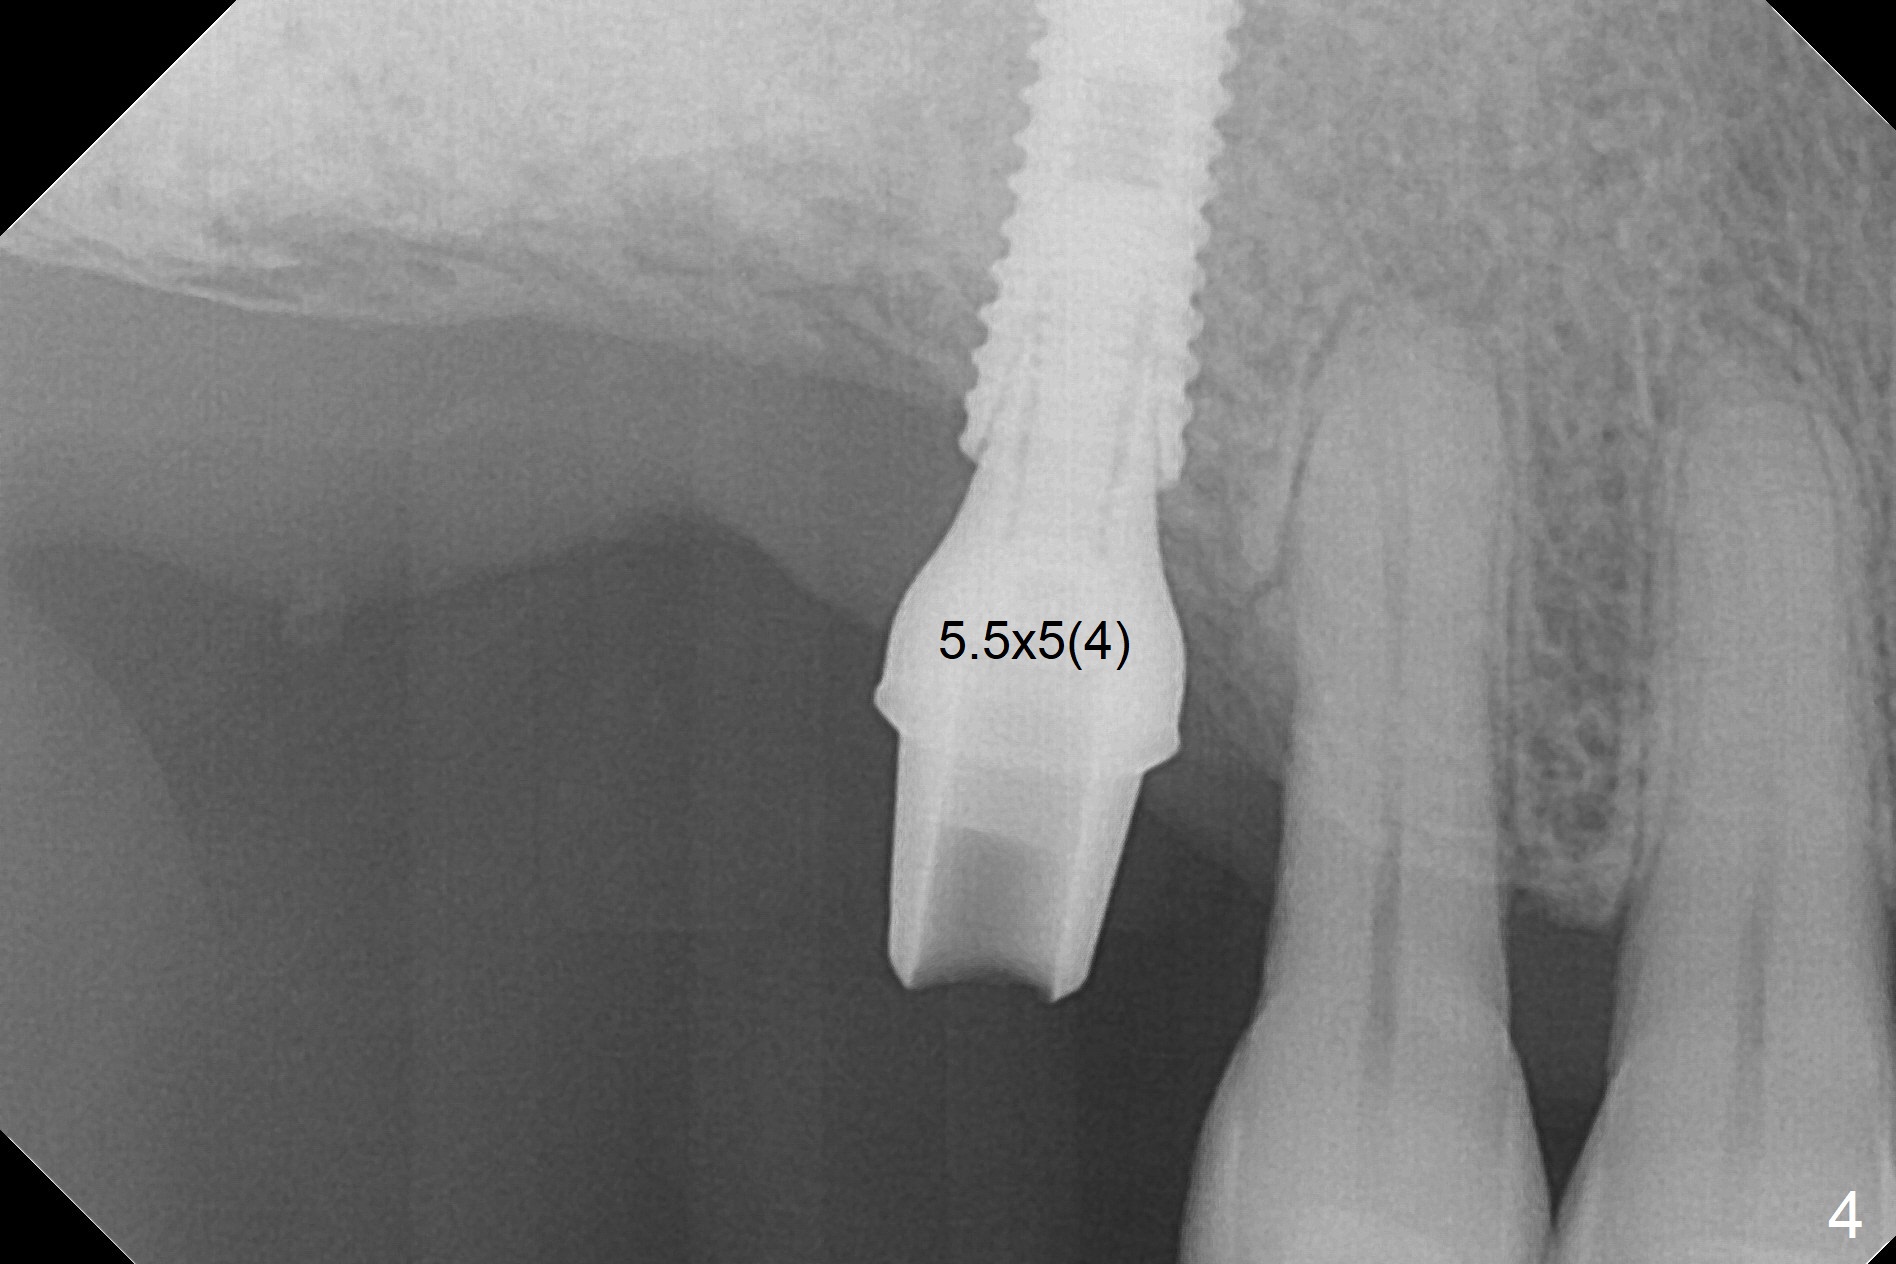

Since the ridge crest at #3 is narrow, Tatum bone scalpels are used to get access and initiate bone expansion, followed by bone blades and RT 2. It seems that the osteotomy starts mesially; bone height being increased (Fig.1). When the apical end of the osteotomy tilts mesially, more bone height is obtained. Drills are alternatively applied because of the hard bone (Fig.2). A 4x13 mm UF implant is placed initially with the distal threads unburied (Fig.3, >50 Ncm). With further seating of the implant, a 5.5x5(4) mm abutment is used (Fig.4), which closes the access. No suture is warranted. An immediate provisional is fabricated for the patient's comfort and psychological effect. In fact, the abutment cuff changes to 5 mm prior to temporarization. There appears no bone loss <4 months postop (Fig.5). Pulpitis develops at #4 due to DO caries 1 year 5 months post cementation (Fig.6 *). The crown at #3 is removed for easy and conservative distal carious removal and Cavit temporary restoration to prevent sodium hypochlorite leakage. Then occlusal access is made for pulpotomy. When RCT finishes, no crown will be made, but occlusal reduction is required. The patient returns for RCT 1 month later (Fig.7,8). Cavit remains in place (Fig.7 C). Although 2 threads are exposed distal (Fig.8 arrow), there is no sign or symptom of periimplantitis, which may be related to the thick gingiva (arrowhead). Return to Upper Molar Immediate Implant, IBS, #14 (Tissue Punch) Xin Wei, DDS, PhD, MS 1st edition 08/25/2017, last revision 09/08/2019